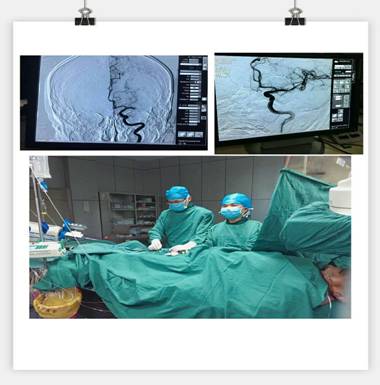

凌晨3點(diǎn)30分, “叮叮?!币魂嚰贝俚碾娫掜戔彺蚱屏松钜沟膶?kù)o。 “你好,這里是急診科,請(qǐng)準(zhǔn)備一張男床,腦血管意外患者”。患者是一名63歲男性,突發(fā)右側(cè)肢體乏力5.5小時(shí),由家屬用輪椅推送入院。入科后患者神志昏睡,心率48次/分,血壓186/100mmHg,NIHSS評(píng)分20分。病人情況十分危急,在劉禮泉主任指示下,患者為急性缺血性卒中,有溶栓指征。在劉主任與家屬談話期間,值班醫(yī)生同時(shí)開出醫(yī)囑,患者予以硝普鈉控制血壓+尿激酶靜脈溶栓。夜班護(hù)士立即給病人抽血、吸氧、心電監(jiān)護(hù)、建立靜脈通道、準(zhǔn)備藥物……我們忙而不亂,默契配合。溶栓過(guò)程中劉主任一直守護(hù)在病人身旁,隨時(shí)觀察病人的病情變化。溶栓后,患者右側(cè)肢體有自主活動(dòng),但乏力癥狀及意識(shí)障礙無(wú)明顯緩解,劉主任立即決定行頭頸聯(lián)合CTA,明確是否有大血管閉塞。果不其然,患者頭部CTA提示左側(cè)大腦中動(dòng)脈M1段栓塞,如果大血管得不到及時(shí)開通,必然會(huì)出現(xiàn)災(zāi)難性的后果。劉主任建議家屬考慮是否行血管內(nèi)治療開通血管,經(jīng)過(guò)耐心細(xì)致的溝通,患者家屬同意行急診腦血管造影檢查及血管內(nèi)治療。 同時(shí)立即召集曾比賢副主任、聶利珞副主任趕來(lái)醫(yī)院,為患者在局麻下行全腦血管造影+顱內(nèi)血管取栓術(shù)。時(shí)間伴隨著沉悶緊張的氣氛一分一秒地過(guò)去,取栓的生命通道終于打開,患者病變血管恢復(fù)良好,手術(shù)圓滿成功,此時(shí)灰暗的天才微微光亮……

在急性腦梗死患者緊急救治中,時(shí)間就是生命,該病例運(yùn)用了動(dòng)靜脈聯(lián)合的方式治療急性腦梗塞,有效地保護(hù)了患者的大腦,此類技術(shù)在國(guó)內(nèi)處于領(lǐng)先治療手段,溶栓、取栓同步進(jìn)行的橋接搶救措施起到了至關(guān)重要的作用。該病例成功取栓意味著我院神經(jīng)內(nèi)科在治療急性腦血管病方面已經(jīng)從傳統(tǒng)的靜脈溶栓向介入取栓的現(xiàn)代化治療方式轉(zhuǎn)變。